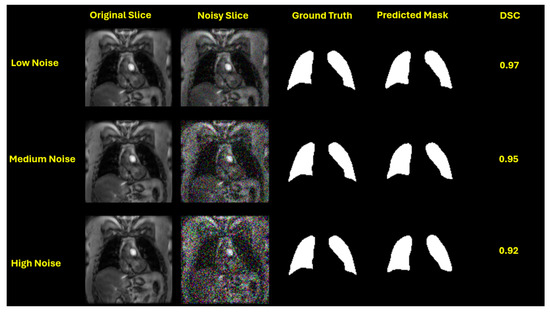

All models were trained using the Adam optimizer and a Dice Cross Entropy Loss function, which is well-suited for addressing class imbalance in segmentation tasks. Early stopping was used to terminate training when the validation loss plateaued, preventing overfitting. To assess model robustness, Gaussian noise [36] was added to the test set at various levels, defined by standard deviations, to simulate the reduced image quality often encountered in clinical practice. This noise was introduced only during testing to evaluate the models’ generalization ability and their performance in noisy, real-world scenarios without compromising the integrity of training. To simulate real-world imaging conditions, we introduced Gaussian noise at four pre-defined levels: no noise (std = 0.0), low noise (std = 0.05), medium noise (std = 0.15), and high noise (std = 0.25). This enabled us to systematically examine how each model performs as image quality degrades due to noise.

This performance trend is visually evident in the qualitative segmentation results shown in Figure 3, Figure 4, Figure 5 and Figure 6. Specifically, Figure 3 and Figure 5 illustrate the robustness of the ViT-based UNet with an MiT-B5 backbone on proton and hyperpolarized gas MRI, respectively, where accurate segmentation is preserved even at high noise levels. In contrast, Figure 4 and Figure 6 highlight the degradation in segmentation quality for the CNN-based UNet with a ResNet-152 backbone, where boundary accuracy and Dice scores drop considerably under increasing noise. These visual examples further support the quantitative findings and reinforce the advantage of transformer-based architectures in noisy clinical environments.